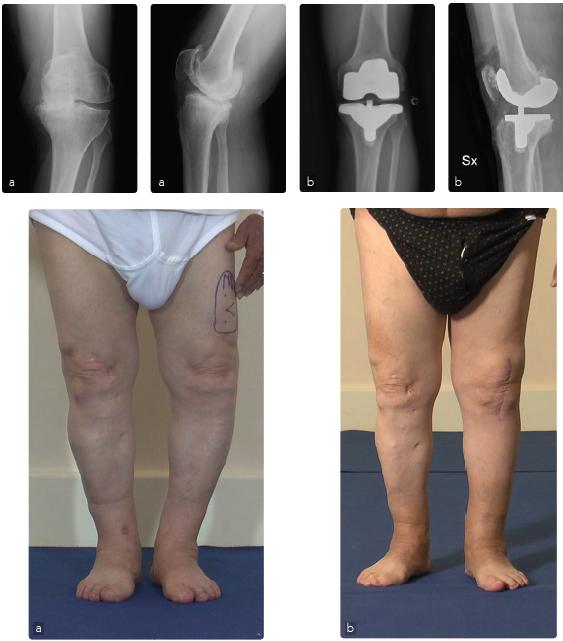

Caso 2: Protesi di ginocchio in grave varismo

Maschio, 57 anni, affetto da gonalgia cronica in ginocchio varo artosico (varismo>30°) (a). La deformità e l'artrosi comportano per il paziente una grave invalidità con difficoltà severa alla deambulazione e all'esecuzione delle normali attività della vita quotidiana. La correzione dell'asse del ginocchio e della artosi è stata ottenuta con l'impianto di una protesi standard (b). Il paziente in seguito all'intervento chirurgico ha ripreso la piena funzione dell'arto operato con scomparsa del dolore.